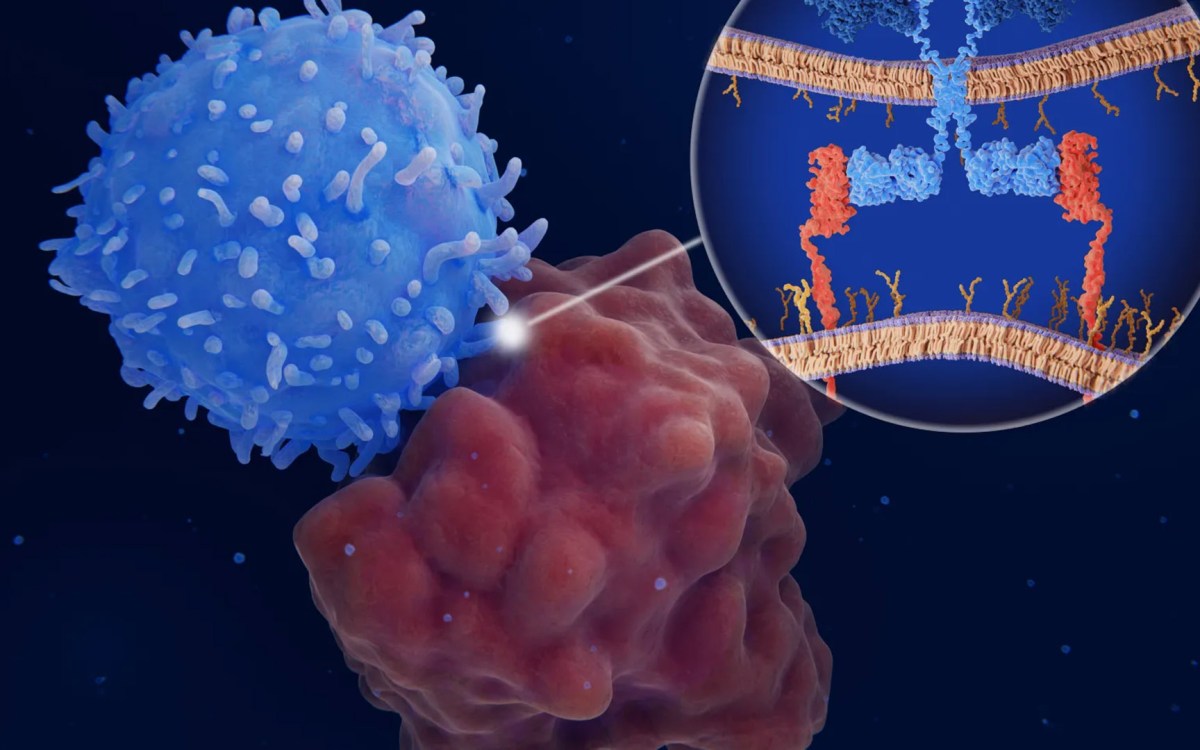

Unlocking the promise of CAR-T

Research on multiple fronts seeks to expand impact of a cancer therapy that has left patients and doctors awestruck